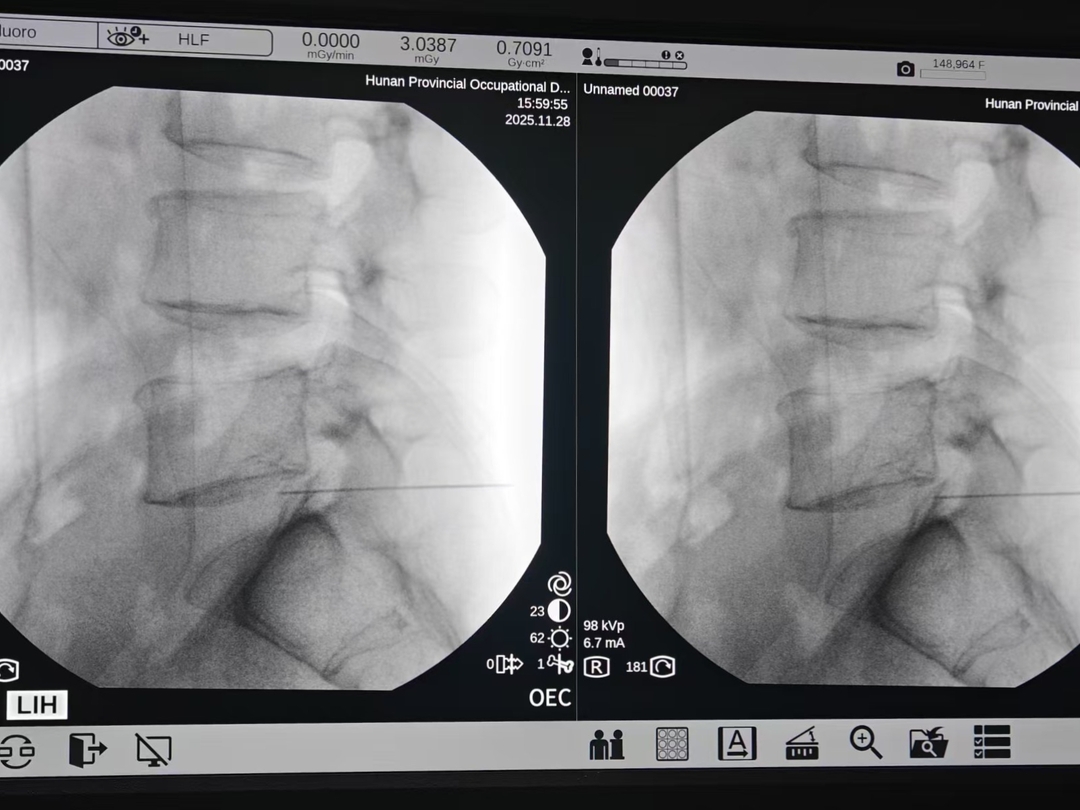

在湖南省职业病防治院(南华大学附属职业病防治院)就诊后,彭先生被确诊为腰椎间盘突出。考虑到他需要长期驾驶的职业特性,且保守治疗效果不佳,医生建议行“腰椎射频消融术”。手术当天,他的腰痛即明显缓解。彭先生感叹:“原来以为一定要开刀,没想到微创也能解决问题!”

手术在C型臂X射线或CT的实时引导下进行,医生能将穿刺误差控制在1毫米以内,像“制导导弹”一样精准命中突出的髓核组织,完全避开正常的神经与脊柱结构,避免了传统手术对脊柱稳定性的影响。